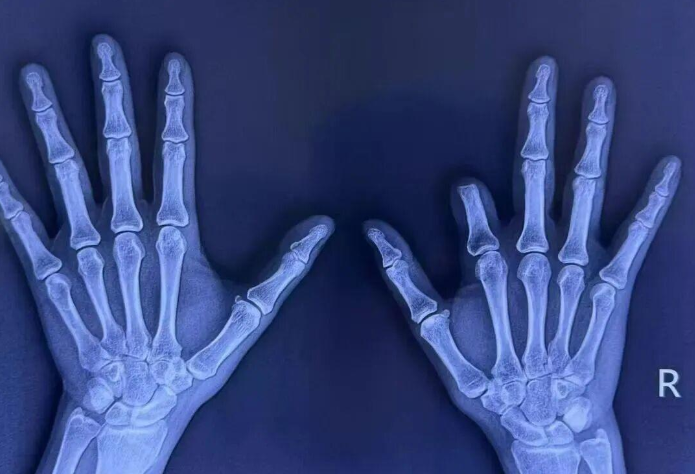

半岛网9月30日讯 (记者 齐娟 纪豪杰)因一年前机器挤压导致右手示指五度缺损,44 岁的叶女士带着一份坚定的希望,从广东到山东,跨越千里,来到莲池骨科寻求治疗。修复重建外科杨志主任团队,创新设计 “组合式” 再造方案,联合多手术组在40倍显微镜下奋战超22小时,为叶女士重获手指的功能与自信。

从广东到山东,跨越千里,44岁的叶女士带着一份坚定的希望来到莲池骨科。一年前,她在劳作时不幸被机器挤压右手,虽经当地医院救治,但右手示指(食指)因严重毁损不得不进行截指手术,导致了示指五度缺损。这不仅影响了手部的抓、握、捏等基本功能,身体完整性的缺失,更是给她的生活、工作和心理带来了巨大负担。经多方打听,她慕名找到莲池骨科修复重建外科的杨志主任,希望通过手指再造技术重获手指的功能与自信。